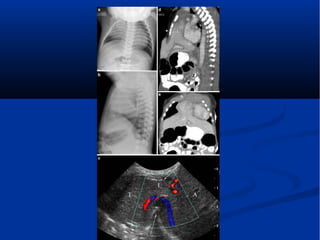

A 7-day-old boy with a

Morgagni hernia. a, b Anteroposterior

(a) and lateral (b) chest

radiographs show a poorly defined

right chest mass and right

upper lung atelectasis. c Sagittal

color Doppler sonogram of the

right chest obtained on the same

day shows herniation of the liver

(L) through an anterior foramen

of Morgagni hernia (arrows).

Note the abnormal course of the

hepatic vein and the difference

in echotexture of the intrathoracic

(T) and intraabdominal (A)

portions of the liver. d, e Sagittal

(d) and coronal (e) contrastenhanced

CT reconstructions

obtained the same day confirm

anterior liver (L) herniation

Hiatus hernia

A 7-day-old boywith a Morgagni hernia. a, b Anteroposterior (a) and lateral (b) chest radiographs show a poorly defined right chest mass and right upper lung atelectasis. c Sagittal color Doppler sonogram of the right chest obtained on the same day shows herniation of the liver (L) through an anterior foramen of Morgagni hernia (arrows). Note the abnormal course of the hepatic vein and the difference in echotexture of the intrathoracic (T) and intraabdominal (A) portions of the liver. d, e Sagittal (d) and coronal (e) contrastenhanced CT reconstructions obtained the same day confirm anterior liver (L) herniation